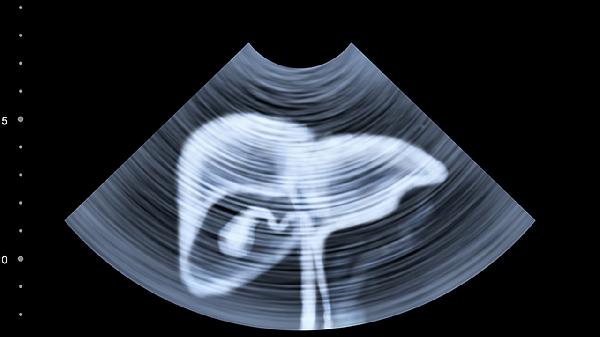

该药含丹参、三七等活血化瘀成分,能抑制肝星状细胞活化,延缓肝纤维化进展。早期肝硬化患者服药后肝硬度值可能改善,但中晚期患者仍需联合抗纤维化西药。需定期进行肝脏弹性检测评估效果。